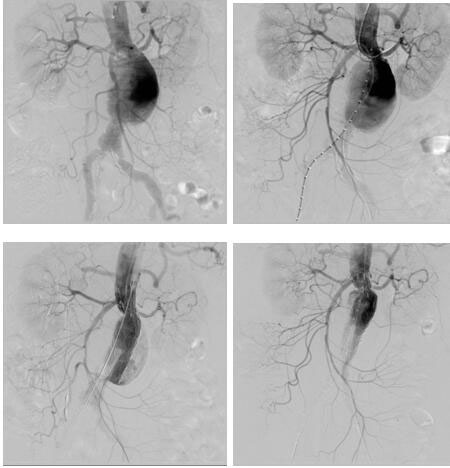

血管介入科完成我院首例腎下復(fù)雜型腹主動(dòng)脈瘤腔內(nèi)修復(fù)

日前,血管介入科為一位患腎下復(fù)雜型腹主動(dòng)脈瘤(左腎動(dòng)脈距離瘤體僅4mm)74歲老年女性完成腎動(dòng)脈煙囪+腹主動(dòng)脈瘤覆膜支架腔內(nèi)隔絕術(shù),術(shù)后恢復(fù)良好。該患者基礎(chǔ)疾病多,已經(jīng)出現(xiàn)腹痛癥狀,腹主動(dòng)脈瘤瘤體隨時(shí)有破裂風(fēng)險(xiǎn),但左腎動(dòng)脈距離瘤體僅4mm,采取傳統(tǒng)開放手術(shù)(腹主動(dòng)脈瘤切除+Y型人工血管置換+左腎動(dòng)脈轉(zhuǎn)流術(shù))手術(shù)創(chuàng)傷大,手術(shù)風(fēng)險(xiǎn)高,經(jīng)血管外科治療團(tuán)隊(duì)反復(fù)研究病例,并在院領(lǐng)導(dǎo)支持下,決定采取腔內(nèi)治療:先經(jīng)肱動(dòng)脈穿刺置鞘于左腎動(dòng)脈留置導(dǎo)絲,再經(jīng)雙側(cè)股動(dòng)脈上導(dǎo)絲導(dǎo)管造影定位,在施放腹主動(dòng)脈主體支架前先經(jīng)左肱動(dòng)脈留置導(dǎo)絲導(dǎo)引下于左腎動(dòng)脈置入VIABAHN支架保證左腎動(dòng)脈供血,再釋放腹主動(dòng)脈主體支架,解決了左腎動(dòng)脈距離瘤體過近的問題。該例手術(shù)的完成,標(biāo)志著我院在腹主動(dòng)脈瘤的腔內(nèi)治療跨入省內(nèi)領(lǐng)先行列。